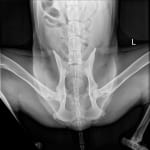

- Mildly decreased range of motion of the hips with crepitus

- No cruciate ligament abnormalities

- Radiographs

- Radiographs are normal